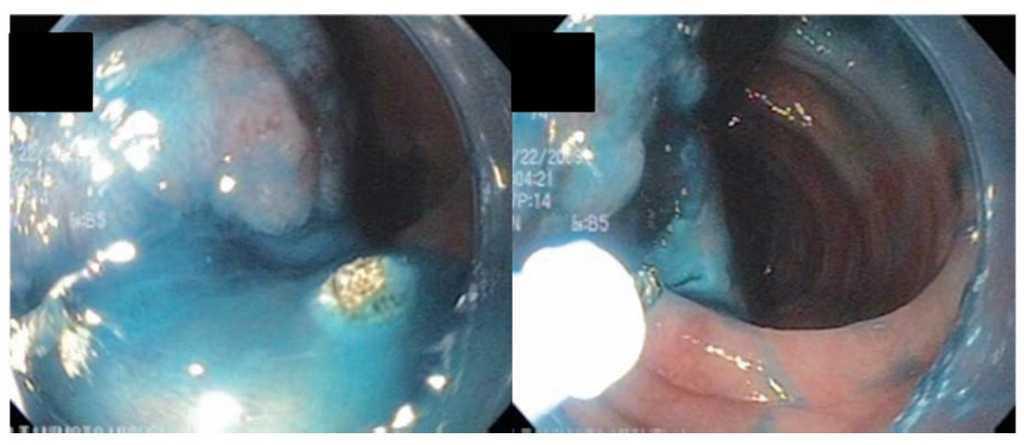

Hombre de 74 años, a quien se realizó colonoscopia por la presencia de sangre oculta en heces. Durante el procedimiento se observó una lesión en colon sigmoides, a 30 cm del margen anal, seudopediculada de base ancha y de aproximadamente 4 cm (Figura 1). Las biopsias informaron adenoma túbulovelloso con displasia de alto grado. Se le propuso cirugía para resección de dicha lesión pero el paciente rehusó este procedimiento y decidió buscar otras alternativas terapéuticas. Después de explicarle los riesgos-beneficios de la disección endoscópica aceptó el procedimiento. Se le solicitaron exámenes de laboratorio, estudios de extensión y valoración preoperatoria con resultados normales-negativos. Se le realizó disección endoscópica de la submucosa con la navaja flexible (Flex-knife), en 60 minutos y sin complicaciones (Figura 2). La pieza obtenida midió cuatro por tres centímetros (Figura 3). Después de 24 horas de hospitalización posprocedimiento, fue dado de alta sin complicaciones.

Figura 1. Lesión en colon sigmoides.

¿ Figura 2. Disección endoscópica de la submucosa con la navaja flexible.